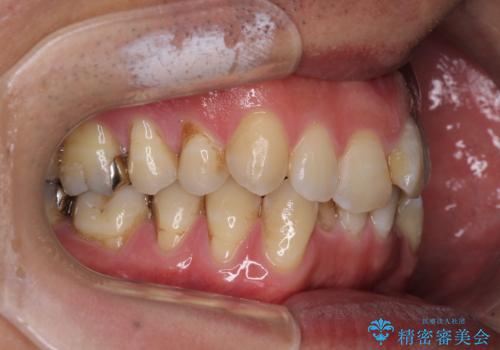

- 患者様

- 30代男性

- インビザライン・審美装置

- 治療期間

- 1年2ヶ月